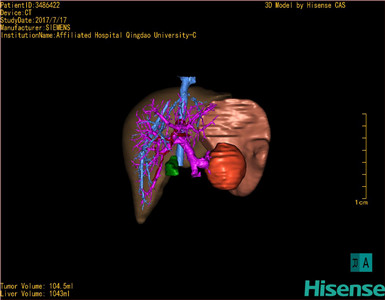

术前三维重建及手术方案设计:

将0.625mm双源薄层CT资料的静脉期和动脉期Dicom格式文件导入海信CAS系统。

通过调节窗宽窗位调整CT序号,对肿瘤,肝实质,胆囊,下腔静脉,肿瘤,肝动脉、门静脉及肝静脉等进行三维重建;系统自动计算肿瘤体积和肝脏体积。

模拟手术操作,自动计算切除肿瘤体积。肝脏体积为1096ml,胰腺肿瘤体积为115.5ml,通过比对12-13岁正常肝脏体积为1116.86±158.78 ml,通过术前模拟手术,精准判断切除后肝脏体积无明显变化,避免肝衰竭发生。

术前三维重建:

重建图片